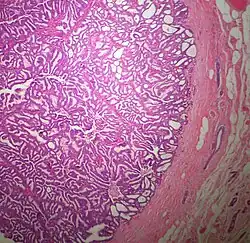

The microscopic histopathology (refer to adjacent high-power photomicrograph) of EPC tissues typically shows papillary structures with fibrovascular cores and proliferating neoplastic epithelial cells growing within cystic spaces, all of which are enclosed within a dense fibrous capsule. In general, EPC tumors do not have areas of neuroendocrine degeneration or myoepithelial cells.[6] The presence of a dense fibrous capsule distinguishes EPC from other papillary breast tumors, particularly PDCIS;[3] the absence of neuroendocrine differentiation areas helps distinguishes EPC from SPC tumors;[3] and the absence of peripherally located myoepithelial cells helps distinguish EPC from PDCIS tumors.[7] EPC tumors may be totally contained within their fibrous capsules or have one or more areas that have invaded through the capsule to normal breast tissues and/or chest muscles; these two variants are termed in situ EPC and infiltrative EPC, respectively.[3][5] In a study of 25 individuals with EPC, 14 had in situ and 11 had invasive disease with 6 of the invasive tumors rated as high grade (see high grade tumors) based on their microscopic histopathology.[5] Rarely, EPC tumors metastasize to nearby sentinel lymph nodes, other nearby axillary lymph nodes, and/or distant tissues; these metastases have in general shown papillary morphologic features similar to their primary tumors.[6] Uncommonly, EPC tumors co-exists with nearby PDCIS,[7] invasive carcinoma of no special type, invasive cribriform carcinoma of the breast, mucinous carcinoma, or tubular carcinoma[3] tumors.